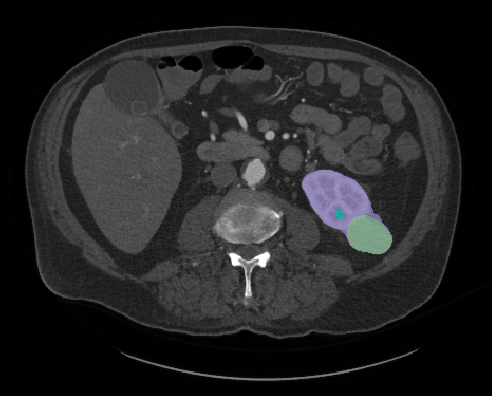

Heller is a PhD student conducting computer science research at University of Minnesota. His research focuses on using computer technology to enhance medical imaging, like a CT scan or an MRI. According to Heller, the magnified images will allow radiologists to quantify the type of tumor it is, saving time between a patient’s diagnoses and treatment.

“They will be able to measure a tumor mass, determine how big and rough they are, and whether they look distinct or blurry against the background. Medical professionals can use that information to choose the most effective treatment and predict a patient's outcome,” Heller explains.

(Courtesy: Nick Heller)

“Then we can turn those numbers into a computer code. If we can automate the code with images and equipment, a radiologist can just hit a button and receive information on the tumor, rather than looking at the image and making a judgement call,” Heller states.